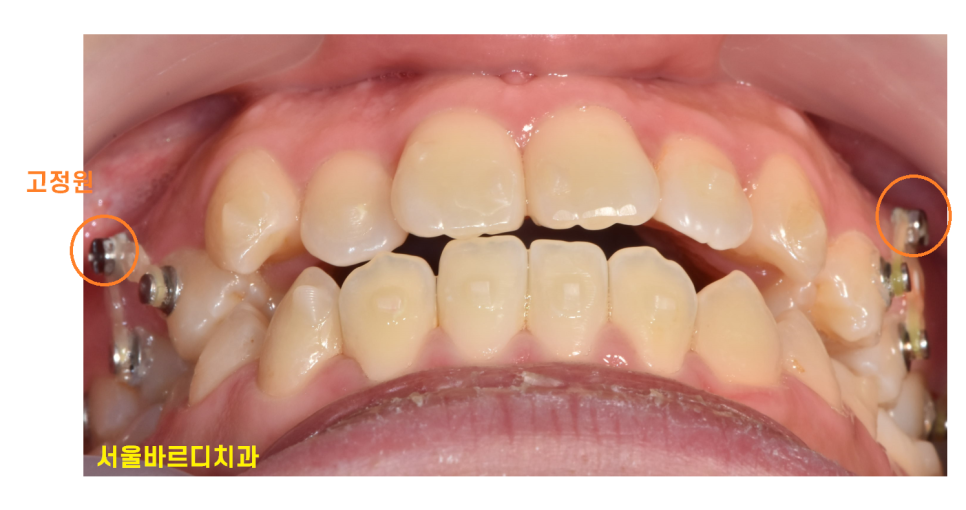

투명 교정 인비절라인으로 불리는 치료는 꼈다 뺐다만 하여

치아가 이동된다 생각하시는 분들이 많습니다.

그렇지만 투명교정 장치만으로는 모든 치아 이동이 완벽히 이루어지기 어려운 경우가 있습니다.

이럴 때는 미니 스크류를 함께 사용하기도 하는데요.

힘을 확실히 주기 때문에

치료 기간이 단축되고 치아 이동이 정확하게 이루어진답니다~!

투명교정 장치를 끼고 나서는 사진과 같은 모습입니다.